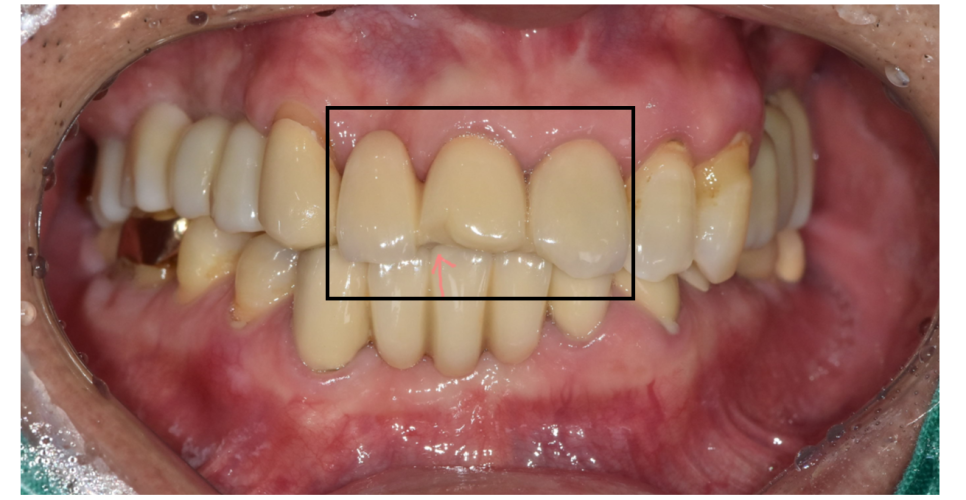

또한 1개 치아가 문제가 생겨도

문제가 생긴 치아를 치료하기 위해

치료한 치아 모두 제거가 필요하다는 단점이 있습니다.

250218 1개 치아가 문제이지만 묶어 둔 브릿지 제거가 필요합니다